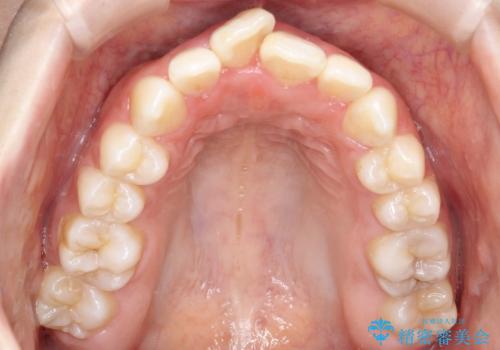

前歯のデコボコと開口を改善し、美しい口元へ

- 前歯のデコボコ(叢生)と、上下の歯が閉じない開口を主訴にご来院されました。精密な検査の結果、歯が並ぶスペースが不足しており、特に奥歯の咬み合わせが安定していないことが開口の原因と判明。患者様と相談し、上下左右の小臼歯を抜歯することでスペースを確保し、審美ワイヤー矯正で全体を整える治療計画を立案しました。これにより、見た目の改善だけでなく、機能的な咬み合わせも獲得することを目指します。

今回の矯正治療では、歯が並ぶスペースを確保するため、上下左右の小臼歯を抜歯しました。装置には目立ちにくい審美ワイヤーを使用し、見た目に配慮しながら治療を進めました。抜歯によってできたスペースを利用して歯を並べ、前歯のデコボコを解消。同時に、歯列全体を動かすことで、上下の歯がきちんと閉じる開口も改善しました。治療期間は約2年間。治療の結果、コンプレックスだった前歯のデコボコと開口が解消され、整った美しい歯並びと、しっかり咬める機能的な咬み合わせを獲得していただけました。